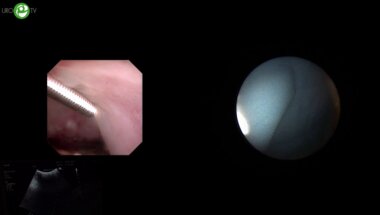

Комбинированная эндоскопическая интраренальная хирургия. Операторы Акопян Г.Н., Панферов А.С.

Акопян Г.Н., Панферов А.С. Эндоскопическая комбинированная интраренальная хирургия

Сорокин Н.И., Акопян Г.Н. - Эндоскопическая комбинированная интраренальная хирургия (ECIRS)